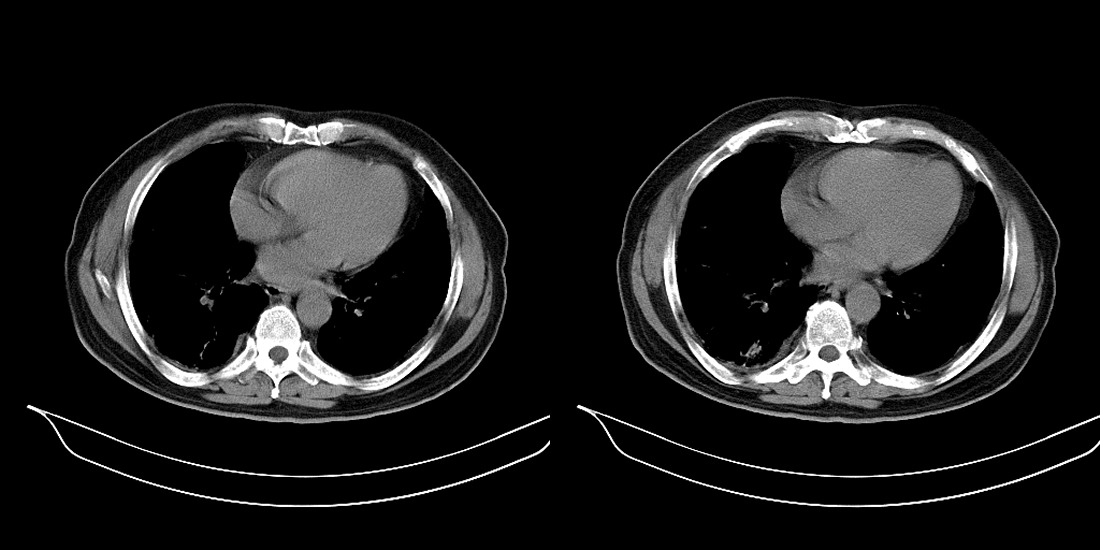

以下是引用zsl6918在2008-2-14 12:15:00的发言:[br]慢支并感染,肺气肿,肺间质纤维化,肺动脉高压。

以下是引用liuyue在2008-2-14 17:25:00的发言:[br]慢支并感染,肺气肿,肺间质纤维化,肺动脉高压 .肺大泡.[br]

以下是引用随光逐影在2008-2-15 11:10:00的发言:[br]1)慢性支气管炎并肺部感染。2)肺间质纤维化。3)肺气肿(多发性肺大泡形成)。4)肺动脉高压。